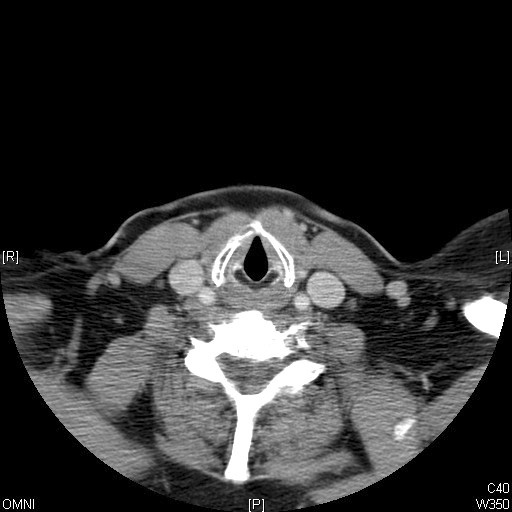

Identify Thyroid, Sternomastoid and Stenohyoid muscles